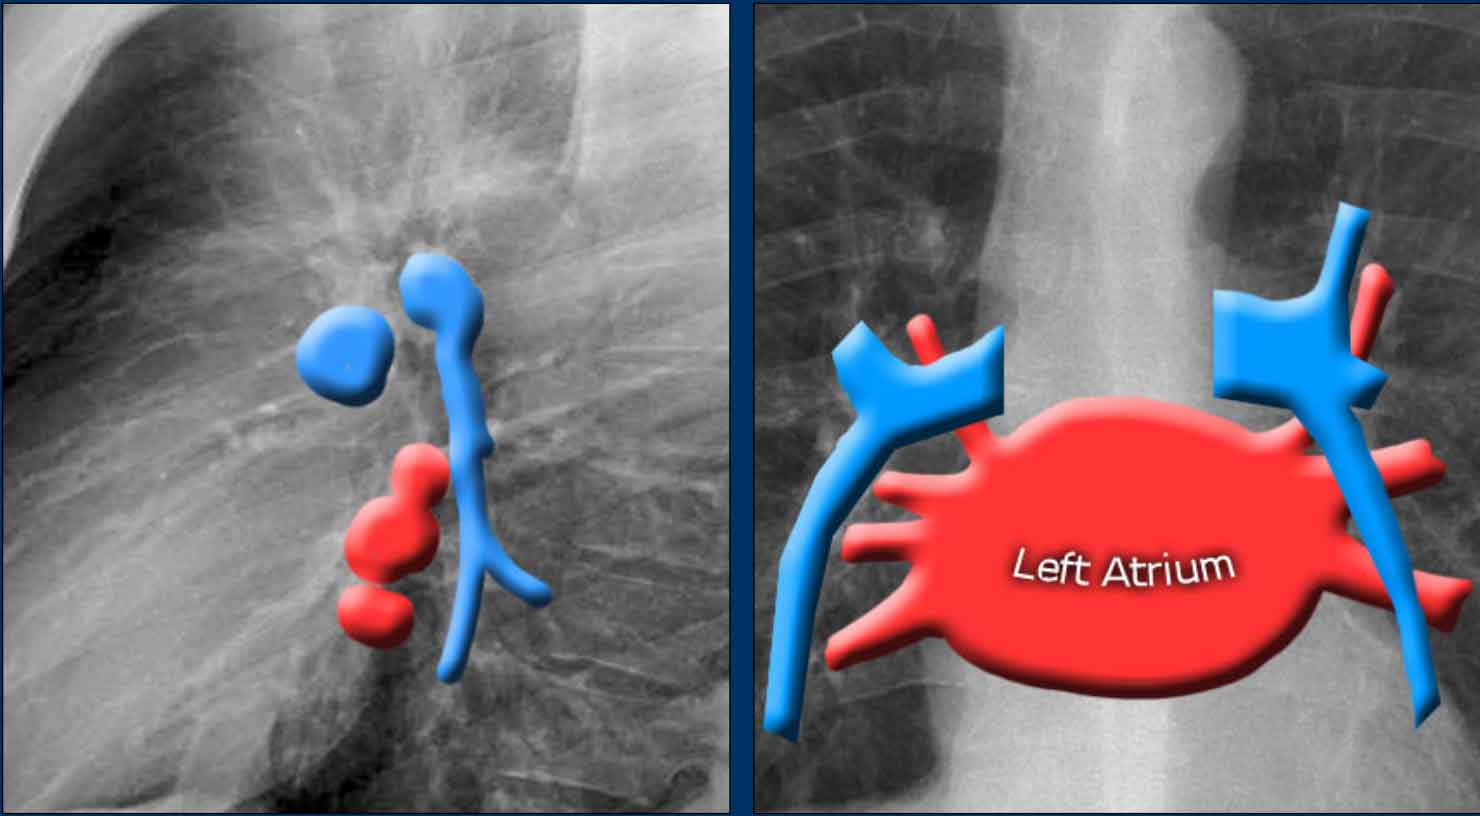

The normal hilar shadow on chest radiography is predominantly vascular in nature—comprising approximately 99% of pulmonary arteries and, to a lesser extent, pulmonary veins (1).

An important anatomical consideration is that the left hilum is normally situated higher than the right.

This relationship arises from the course of the pulmonary arteries: the left pulmonary artery arches over the left main bronchus, while the right pulmonary artery courses anterior to the right main bronchus, which is typically positioned lower than its left counterpart.

In a minority of cases, the hila may be at the same level, but the right hilum should never be higher than the left.

In this illustration, lower lobe pulmonary arteries are colored blue to indicate deoxygenated blood.

These arteries have a more vertical orientation compared to the pulmonary veins, which run more horizontally toward the left atrium, located inferior to the level of the main pulmonary arteries.

On lateral chest radiographs, both pulmonary arteries and veins are identifiable and should not be misinterpreted as lymphadenopathy. Occasionally, pulmonary veins may appear prominent.

The left main pulmonary artery passes superior to the left main bronchus and lies higher than the right pulmonary artery, which courses anterior to the right main bronchus.